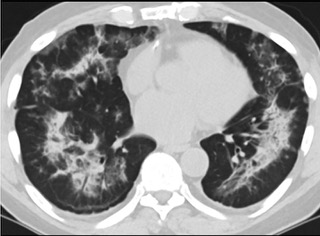

6天后的軸向CT平掃圖像顯示毛玻璃影變?yōu)閷嵶兒洼p度結(jié)構(gòu)扭曲。(同一病人CT影像)